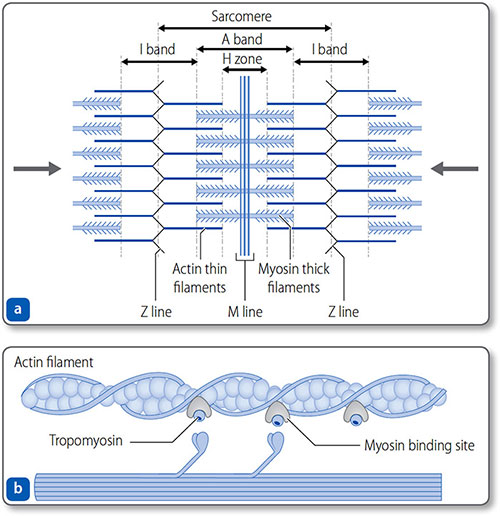

Myofibrils

Myocytes contain elongated myofibrils composed of functional units called sarcomeres (Figures 1.25 and 1.26). Each sarcomere is bounded at each end by a Z line and contains contractile filaments made of the proteins actin and myosin. Peripherally, actin thin filaments attach to the Z line. Centrally, myosin thick filaments interdigitate (i.e. overlap) with the actin filaments.

Figure 1.25: The sarcomere. (a) The sarcomere is bound by the Z lines – formed by the arbed ends of thin actin filaments. The filaments project centrally, where they interdigitate with thick myosin filaments. This gives the striated appearance of cardiomyocytes, defined by the M line, the H zone and the A and I bands. (b) Actin−myosin interaction.

Figure 1.26: Sarcomeres and the sliding filament mechanism of myocardial contraction. Within the sarcomere, the central thick myosin filaments are surrounded by the thin actin filaments. Contraction of the many myocardial sarcomeres underlies contraction, and causes the H band to disappear, the A band to increase and the I band to shorten.

Sarcolemma

The cell membrane – the sarcolemma – invaginates deeply into the myocyte around the Z lines to form T tubules. These are closely associated with sarcoplasmic reticulum, which contains intracellular stores of Ca2+. This enables the rapid coupling of membrane (i.e. T tubule) depolarization with the release of Ca2+ from the sarcoplasmic reticulum to stimulate myofibril contraction.

Myofibril contraction

Thin filaments consist of actin, tropomyosin and troponin complexes (Figure 1.27).

- Troponin T attaches each troponin complex to the tropomyosin

- Troponin I inhibits the binding of myosin heads to actin

- Troponin C binds to Ca2+.

The binding of Ca2+ to troponin C exposes the myosin-binding site, allowing actin−myosin cross-bridges to form.

The sliding filament model of contraction The myosin ‘power stroke’ pulls the filaments so that they slide in opposite directions; this sliding shortens the sarcomere and in turn contracts the myocardium. Cycles of myosin-head binding to actin, contracting, disconnecting and then reattaching – a ‘ratcheting’ effect – progressively shorten the sarcomere as long as intracellular Ca2+ remains high. Both contraction and relaxation are energy dependent 39(ATP consuming). In the heart this is a continual cycle hence the large concentration of mitochondria and glycogen stores.